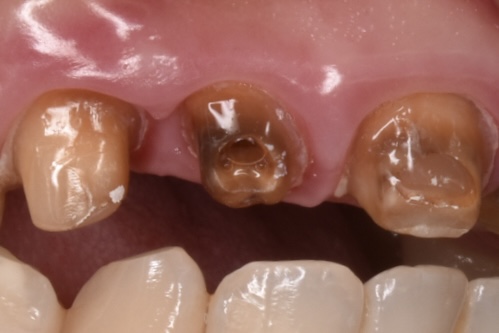

穴だけ開いた歯の状態

神経処置が未処置のまま放置?の歯です。実は下のCTの写真でわかる様に歯の変形があります。ご本人様にお伺いしたところ昔前歯を強打した経験があるとの事でしたが、当時は受診せず経過を診ていたそうです。セラミック治療した歯科ではこの変形した歯について何も伝えられなかったと。。。

ここからは私の推測ですが、、、神経の管の中にビタペックス(消毒効果のある根管充填材)の様なものが確認出来ました。神経治療をトライしてレッジを作ってしまい治療できなかったのでビタペックスを根充材として入れてレジンで蓋をしたのだろうと思います。

この歯については当院でもかなり時間をかけて慎重にマイクロスコープ下で治療のトライをしましたが根の先までは到達出来ませんでした。(これについてもちゃんと治療前に説明しています。今後の治療方針も事前に説明しており、経過が悪ければ歯根端切除や抜歯→インプラントかブリッジか入れ歯の補綴になる事ご了承済です)